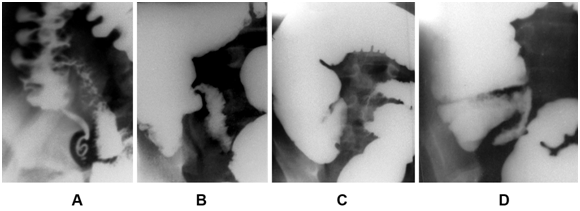

Figure 3 Radiographs of appendixes. (A). Radiograph of unchanged appendix uniformly filled with barium. (B).In two destructive AX are the radiocontrast (calcified) fecal stones. The parts of AX located distal to fecal stones are widened. In the lower AX, after opening the lumen two cavities, contrasted by air, are determined. Contrasting fecal stone lies next to the AX. (C).The oval X-ray-negative formation (fecal fragment) occludes the enlarged cavity at the apex of the AX. (D). Radiograph of destructive AX without foreign inclusions, but with an extended lumen filled coarsely modified mucosa.

The width and its lumen at the distal part of the AX in destructive AA was significantly wider than in norm. The thickness of the wall is on average 0.25 cm. The contrast stones were found in 8 cases, low-contrast - in 12, X-ray negative - in 8, disparate contrast inclusions - in 10, foreign bodies - in 2 and unformed stools 2 observations (Figure 3B & C). Thus, fecal stones and foreign bodies were found in 42 (65%) of 65 patients with destructive AA. As a rule, the width of the stones was much larger than the width of the lumen of the cranial part of the AX. In 20 observations, despite the absence of any inclusions, the width of the closed cavity was much wider than the norm, or, despite the use of high pressure, it was impossible to introduce a contrast agent into the zone of the greatest inflammation. The relief of the mucosa in them was rough, indicating sclerotic changes (Figure 3D). Only in 3 (5%) observations with phlegmonous appendicitis the PX did not differ from normal ones.

All results in the "simple appendicitis" group were the same both in the presence of histological signs of inflammation, and without it. The wall thickness averaged 0.15cm. This allowed us to estimate the data obtained in this whole group as a norm. The lumen of the AX was passable and uniform throughout its entire length (Figure 3A).